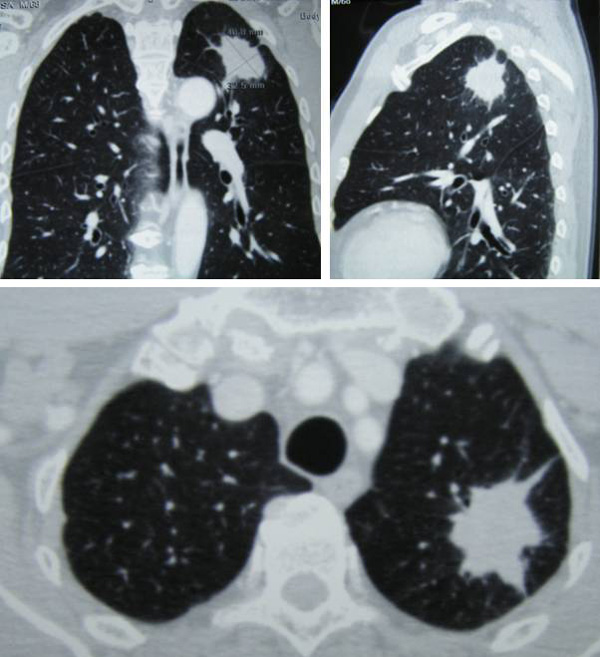

LS was a 71-yer-old man from Indonesia. In 2007, a chest X-ray showed a spot in his left lung. He did not do anything about it. In November 2010, LS did another chest X-ray and the spot was still there. He came to Melaka and did a CT scan on 15 November 2010. There was a speculated soft tissue lesion in the apex of the upper lobe of his left lung. It was 4.0 x 3.3 cm in size and was consistent with a lung carcinoma. A CT guided FNA biopsy was performed and confirmed that it was cancerous.  LS was asked to undergo chemotherapy and radiotherapy. He refused.   LS went to Singapore for a second opinion in February 2011. Another CT scan was done. The tumour had grown bigger to 40 x 35 x 45 mm. He refused further medical intervention and came to seek our help on 13 March 2011.

As I am writing this story, I remember  another case of lung cancer. This man – THK – is 57 years old and he was diagnosed with lung on 22 March 2011. The tumour was 20 x 24 x 22 mn in the upper lobe of his right lung (Note; LS had 40 x 35 x 45 mm) THK underwent 6 cycles of chemotherapy with Gemzar + Cisplatin (total cost about RM 50,000).  The treatment did not cure him. In fact the cancer became more aggressive. He was switched to oral chemo – Tarceva for three months. The PET scan showed further deterioration. He was asked to undergo 6 cycles of chemotherapy with the latest or newest drug, Alimta at RM 9,000 per cycle. THK received 2 cycle of Alimta and gave up. The tumour makers kept rising in spite of the treatment. On 4 January 2012, his CEA was at 666.5 and CA 19.9 was 4,422.0.  In short, the treatment failed miserably. THK concluded he was on the wrong path and came to seek our help on 3 February 2012.